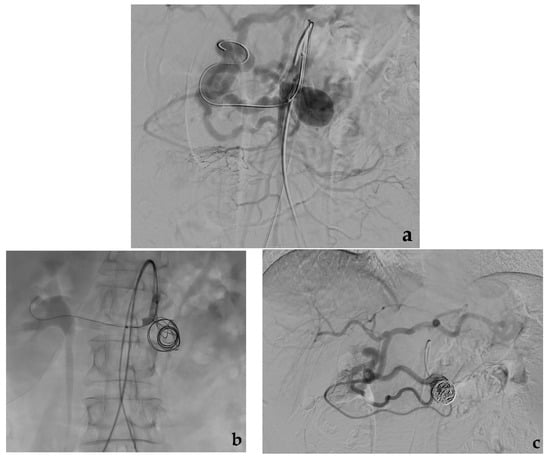

- Secco, G.; Chevallier, O.; Falvo, N.; Guillen, K.; Comby, P.O.; Mousson, C.; Majbri, N.; Midulla, M.; Loffroy, R. Packing technique with or without remodeling for endovascular coil embolization of renal artery aneurysms: Safety, efficacy and mid-term outcomes. J. Clin. Med. 2021, 10, 326. [Google Scholar] [CrossRef]

- Ma, T.; He, Y.; Zhong, W.; Luo, G.; Li, Q.; Wang, Z.; Zhang, H.; Wu, Z.; Qiu, C. Mid-term results of coil embolization alone or stent-assisted coil embolization for renal artery aneurysms. Ann. Vasc. Surg. 2021. [Google Scholar] [CrossRef]